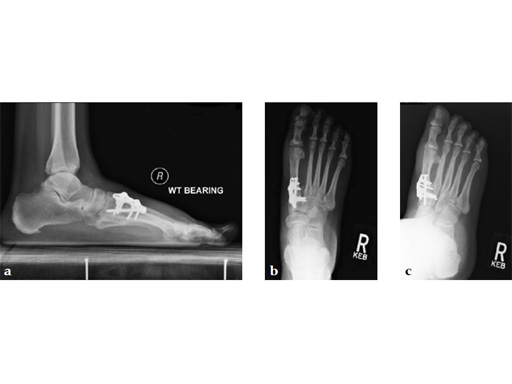

A 46-year-old obese woman with coronary artery disease had sustained a Lisfranc injury while performing an exercise program. She was unable to weight bear and used an electric scooter.

In an effort to restore her ability to exercise and taking into consideration her body weight and upper extremity weakness, a decision was made to use the variable angle locking compression plate. These postoperative x-rays were obtained at 3 months, one month after beginning weight bearing. The patients pain was reduced and she was able to resume a progressive exercise program after 4 months following surgery.

Case provided by Michael Castro, Scottsdale, Arizona